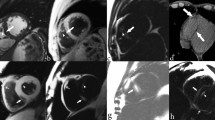

Clinical data reviewed included medical records, echocardiography, plain radiographs, and magnetic resonance imaging of the entire spine. Patients were divided into groups based on gender (male vs. female), age (6–10 vs. 11–18), ethnicity (Han vs. Minority), BMI (Emaciation vs. Normal vs. Overweight/Obesity), chest aspect ratio (< 0.45 vs. ≥0.45), altitude (< 2000 m vs. ≥2000 m; altitude refers to the elevation above sea level of the patients’ long-term residence), main site of scoliosis (Thoracic vs. Thoracolumbar vs. Lumbar), severity (Cobb angle < 90°(Deformed) vs. Cobb angle ≥ 90°(Highly deformed)), and main direction of scoliosis (Left vs. Right).

Among the patients, 12 (4.15%) had congenital heart disease, with the most common type being atrial septal defect (ASD, 1.73%), followed by patent foramen ovale (PFO, 0.69%), ventricular septal defect (VSD, 0.35%), and persistent left superior vena cava (PLSVC, 0.35%) (Table 2). Additionally, 88 patients (30.45%) exhibited cardiac abnormalities related to heart valves. The most prevalent condition was mild tricuspid regurgitation (TR, 17.65%), followed by mild tricuspid and mitral regurgitation (TR + MR, 10.03%), mild mitral regurgitation (MR, 1.04%), and mild aortic valve regurgitation (AR, 0.69%) (Table 3).

Given the anatomical proximity between the thoracic vertebrae and the heart, we further analyzed the relationship between the direction and severity of thoracic curvature and the occurrence of cardiac abnormalities in 192 patients primarily characterized by thoracic curvature. Among them, 10 patients had congenital heart disease, accounting for 5.21%, and 51 patients had cardiac abnormalities related to heart valves, accounting for 26.56%. The occurrence of congenital heart disease and cardiac abnormalities related to heart valves in patients with predominantly thoracic curvature was not related to the Cobb angle of the thoracic curve (P = 0.535 and 0.094, respectively). There was no significant difference in the proportion of congenital heart disease between groups divided by the direction and severity of thoracic curvature (P = 0.845, 0.806). However, the proportion of cardiac abnormalities related to heart valves was higher in the left curvature group compared to the right curvature group (P < 0.05). There was no significant difference in the proportion of cardiac abnormalities related to heart valves between the highly deformed (≥ 90°) group and the deformed (< 90°) group (P = 0.806).